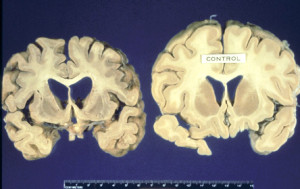

La malattia di Creutzfeldt-Jakob, più nota con il nome di morbo della mucca pazza, è tornata a far parlare di sé anche in Italia.  Nei giorni scorsi si è infatti diffusa la notizia di un caso sospetto in Campania, dove nel mese di giugno un uomo ha incominciato ad accusare i primi malesseri che l’hanno portato, infine, al ricovero d’urgenza all’ospedale Rummo di Benevento prima e al trasferimento, poi, al Cotugno di Napoli, da cui è stato dimesso senza, però, aver ricevuto una diagnosi certa.

Secondo quanto si legge in una nota diffusa dall’Asl di Benevento “in considerazione dell’età del paziente nonché dell’andamento progressivo della sintomatologia, è stato posto il sospetto di patologia degenerativa subacuta del Snc (in particolare una encefalopatia spongiforme)”. Fra le ipotesi è emersa anche quella secondo cui la patologia potrebbe essere stata contratta dall’uomo in Germania, durante un recente viaggio di lavoro. Tuttavia, come sottolinea l’Istituto Superiore di Sanità, il periodo di incubazione del morbo della mucca pazza varia dai 4 ai 40 anni, fatto che unito ai controlli eseguiti sui bovini e alle stime secondo cui il bestiame sarebbe stato infettato verso gli anni ’90 porta gli stessi esperti a ritenere molto improbabile che si tratti realmente di un caso di Creutzfeld-Jakob associato al consumo recente di carne infetta.